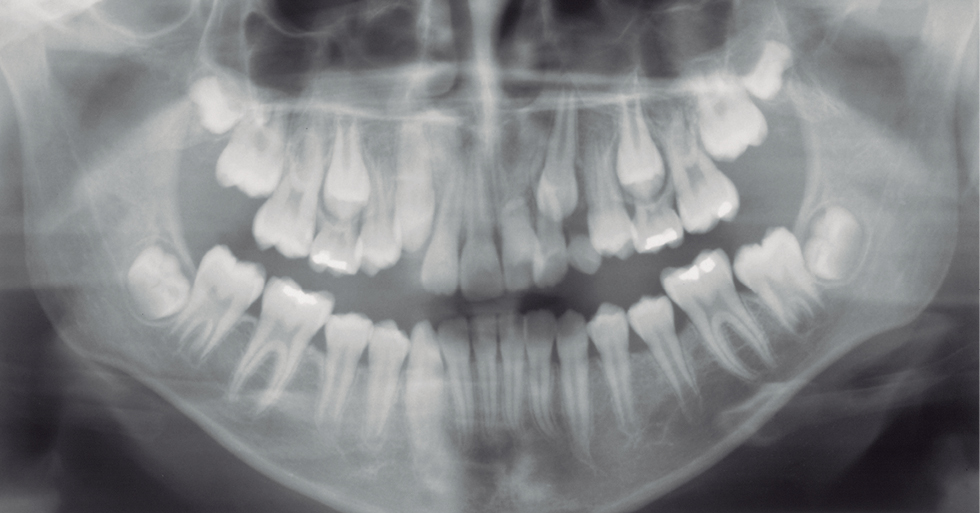

Figura 1: Radiografia panorâmica realizada aos 11 anos e 5 meses.